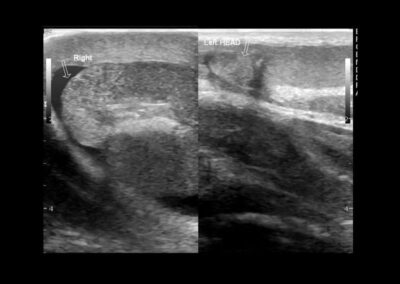

Eine genaue Anamnese und klinische sowie Ultraschalluntersuchung sind die Voraussetzungen für die richtige Diagnose. Immunsuprimierte Patienten (HIV) oder Patienten mit vorheriger Tuberkulose müssen erkannt werden. Die Urinuntersuchung kann einen Schlüssel für die mögliche Ursache geben. Die Symptome der Nebenhodenentzündung können innerhalb von 10 Tagen verschwinden, jedoch kann es bis zu 6 Wochen dauern, bis die Hoden sich wieder normal anfühlen. Die Spermienqualität kann sich vermindern. Das kann allerdings erst mindestens 6 Wochen nach einer Heilung festgestellt werden.

Wenn die Gefahr einer Vereiterung droht, werden wir Ceftriaxon oder Tobramycin verschreiben. Dabei ist eine Ultraschalluntersuchung alle 3-4 Tage erforderlich. - Hoden-Hochlagerung

Die Nebenhodenentzündung ist eine meistens akute Erkrankung des jungen Mannes, oder bei Senioren, wo sie durch obstruktive Ursachen wie die vergrößerte Vorsteherdrüse oder Harnröhrenenge auftreten kann. Sie verursacht Schmerzen, Schwellung, Fieber und gelegentlich Vereiterung. Die Erkrankung muss mit Kühlung, Hoden-Hochlagerung und Antibiotika behandelt werden. Hingegen wird eine vereiterte Epididymitis von Dr. Elseweifi nur chirurgisch behandelt. Die Nebenhodenentzündung verursacht in seltenen Fällen chronische Verhärtungen, jedoch ist deren Einfluss auf die Fertilität wissenschaftlich nicht erwiesen.